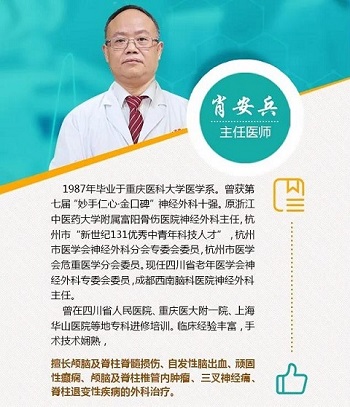

肖/主/任/介/绍